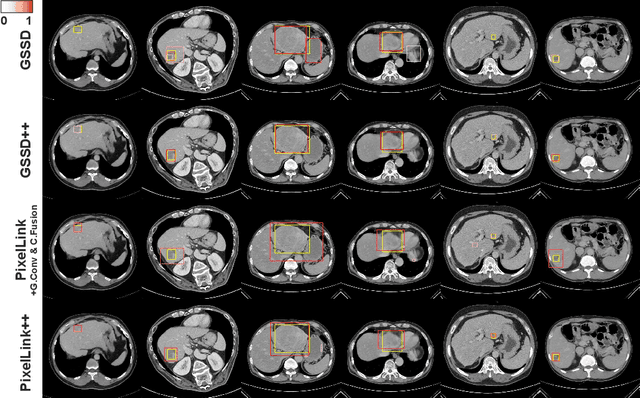

Abstract:The computer-aided diagnosis of focal liver lesions (FLLs) can help improve workflow and enable correct diagnoses; FLL detection is the first step in such a computer-aided diagnosis. Despite the recent success of deep-learning-based approaches in detecting FLLs, current methods are not sufficiently robust for assessing misaligned multiphase data. By introducing an attention-guided multiphase alignment in feature space, this study presents a fully automated, end-to-end learning framework for detecting FLLs from multiphase computed tomography (CT) images. Our method is robust to misaligned multiphase images owing to its complete learning-based approach, which reduces the sensitivity of the model's performance to the quality of registration and enables a standalone deployment of the model in clinical practice. Evaluation on a large-scale dataset with 280 patients confirmed that our method outperformed previous state-of-the-art methods and significantly reduced the performance degradation for detecting FLLs using misaligned multiphase CT images. The robustness of the proposed method can enhance the clinical adoption of the deep-learning-based computer-aided detection system.

Abstract:We present a focal liver lesion detection model leveraged by custom-designed multi-phase computed tomography (CT) volumes, which reflects real-world clinical lesion detection practice using a Single Shot MultiBox Detector (SSD). We show that grouped convolutions effectively harness richer information of the multi-phase data for the object detection model, while a naive application of SSD suffers from a generalization gap. We trained and evaluated the modified SSD model and recently proposed variants with our CT dataset of 64 subjects by five-fold cross validation. Our model achieved a 53.3% average precision score and ran in under three seconds per volume, outperforming the original model and state-of-the-art variants. Results show that the one-stage object detection model is a practical solution, which runs in near real-time and can learn an unbiased feature representation from a large-volume real-world detection dataset, which requires less tedious and time consuming construction of the weak phase-level bounding box labels.